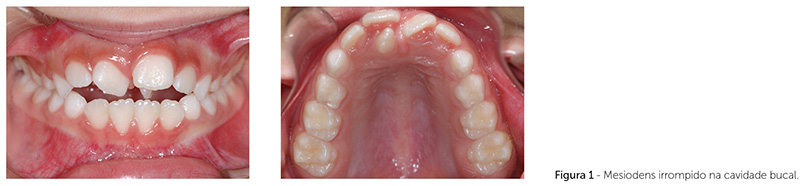

O termo mesiodens refere-se aos dentes supranumerários localizados na região da pré-maxila, exatamente entre os incisivos centrais superiores (Fig. 1 e 2). São os mais frequentes entre os dentes supranumerários1,2. A prevalência do mesiodens na literatura é variada, e tem sido estimada de 0,15 a 7,8% (Tab. 1). Sua prevalência é maior no sexo masculino, numa proporção aproximada de 2:13-10. Embora sua etiologia não tenha sido estabelecida, menciona-se na literatura a possibilidade genética, dada a sua recorrência familiar4,11,12,13. Tem sido sugerido um traço autossômico dominante, com falta de penetrância em algumas gerações13, e uma herança ligada ao cromossomo X devido à alta prevalência nos homens.

Na maioria das vezes, o mesiodens é um dente solitário3,4,5,7,14 e dismórfico11, mas que pode variar em morfologia desde uma forma rudimentar cônica de tamanho reduzido, mais frequente4,7,8,9,14,18, até uma forma complexa com vários tubérculos. Raramente o mesiodens irrompe espontaneamente8,10,14,17. Sua erupção apenas ocorre nas situações em que o mesiodens está voltado para o plano oclusal. Na maioria das vezes, o mesiodens está invertido, com a coroa voltada para a cavidade nasal e o ápice radicular voltado para a cavidade bucal3,8,9. Sua presença pode ocasionar desordens locais, sendo as mais comuns o atraso ou impedimento da erupção de dentes, deslocamento ou rotação dos dentes adjacentes, desenvolvimento de cistos dentígeros, reabsorção de raízes adjacentes, apinhamento, diastema ou dilaceração dos dentes permanentes1,3,4,5,7-11,14,17.